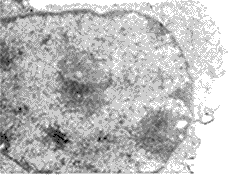

经100 μmol/L H2O2作用1 h后,完全培养液继续培养3 h的PMVEC,透射电镜观察,可见部分细胞中有早期的核固缩现象(图3)。偶见不典型的凋亡小体。

Fig 3 Nucleole of PMVEC treated with H2O2 for 1h,then cultrured with 20% FBS cultrue medium for 3 h(Transmission electron micrograph)

图3 H2O2作用后PMVEC细胞核透射电镜